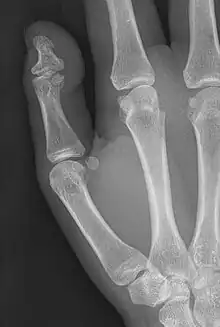

| Brachyphalangy of the thumb's distal phalanx, also known as brachydactyly type D, with otherwise normal phalanges of the 2nd-5th digits | |

Brachyphalangy of the distal phalange of the thumb

This condition is caused by either fusion or early closure of the phalange's growth plate. One example is brachydactyly type D, which is caused by an early closure of the thumb's distal phalange, leading to a congenitally short thumb with a similarly short and wide thumb nail.